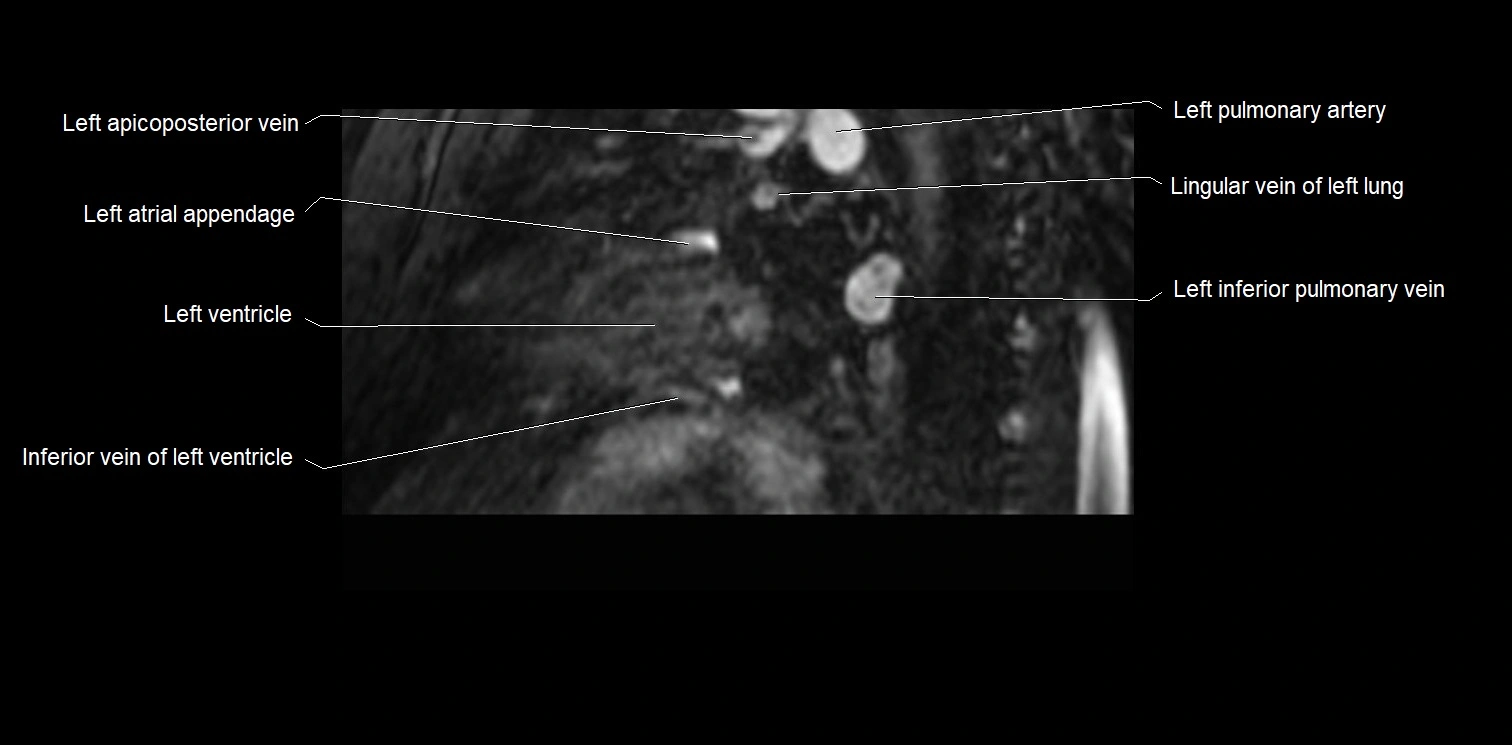

MRI image